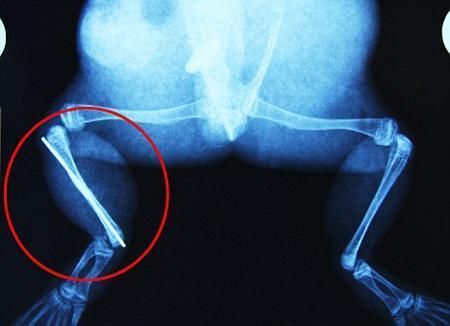

環(huán)球網(wǎng)4月2日?qǐng)?bào)道 據(jù)《每日郵報(bào)》報(bào)道,上個(gè)月,南非大牛蛙布魯萊的右小腿被鄰居家的一只狗咬到,導(dǎo)致粉碎性骨折,現(xiàn)在經(jīng)過(guò)2個(gè)小時(shí)的手術(shù),它的斷腿已經(jīng)被接上,它也因此成為有史以來(lái)第一只通過(guò)外科手術(shù)用鋼針接上斷腿的青蛙。

野生生物專家安妮經(jīng)常為學(xué)校寫教材,她認(rèn)為這是人類第一次通過(guò)手術(shù)給一只青蛙接斷腿。在手術(shù)開始階段,獸醫(yī)把少量給狗用的麻醉藥注入到這只青蛙體內(nèi),讓它失去知覺。然后他在布魯萊的斷腿上切開一個(gè)小口,把一根小鋼針植入腿里。最后獸醫(yī)給它縫了9針,把切口縫合在一起。僅僅幾周后,布魯萊就能在安妮家附近活動(dòng)了。這只青蛙大約已有25歲,主要以嚙齒動(dòng)物、蛇和其他青蛙為食。布魯萊所屬的牛蛙種群正在不斷減小,目前只能在非洲南部的濕地里才能看到這種青蛙。